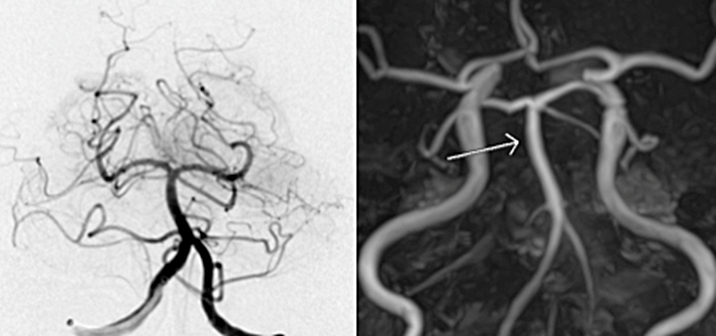

一つは“ステント”と呼ばれる金網を用いる方法、もう一つは“吸引カテーテル”と呼ばれる、文字通り血栓を吸引して除去する方法があります。

ステントは心筋梗塞や狭心症の時に細くなった心臓の血管を広げる時に使われているものとして知られております。ただ、血栓回収療法の時は少し違った使い方をします。血栓で詰まったところでステントを広げると、ステントが広がり血栓を押しつぶします。すると一時的に脳の血流が再開します。ただ、このまま様子をみるとステントの金網の中に血栓がめり込みます。そのうちめり込んだ血栓により再度血管が詰まってしまいます。これでは意味が無いのでは、と思ってしまいますが、再度詰まることでステントが血栓に絡んだと判断できます。そうすれば、このステントをゆっくり引くとステントに絡んだ血栓も一緒に引けて来て、ステントを抜去すると血栓も取り除くことができます。うまくいけば、1回で詰まった血栓を除去できます。

再開通しない場合、さらに狭窄の程度が悪化することがあります。最近の報告での再開通率は58-88%と様々な報告があります。さらにいったん再開通しても再度閉塞を来すこともあります(これを防止するための治療は致します)。もちろん再開通が無ければ症状の改善は期待できず、症状の悪化を阻止することも困難になります。運動麻痺、感覚障害、言語障害、視覚障害、高次機能障害が進行し、最悪の場合には生命の危険も伴います。